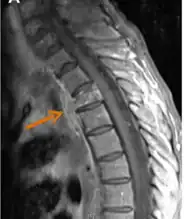

The diagnosis of actinomycosis can be a difficult one to make. In addition to microbiological examinations, magnetic resonance imaging and immunoassays may be helpful.[10]

- Contrast-enhanced magnetic resonance images showing contiguous spread of pulmonary actinomycosis to the spine